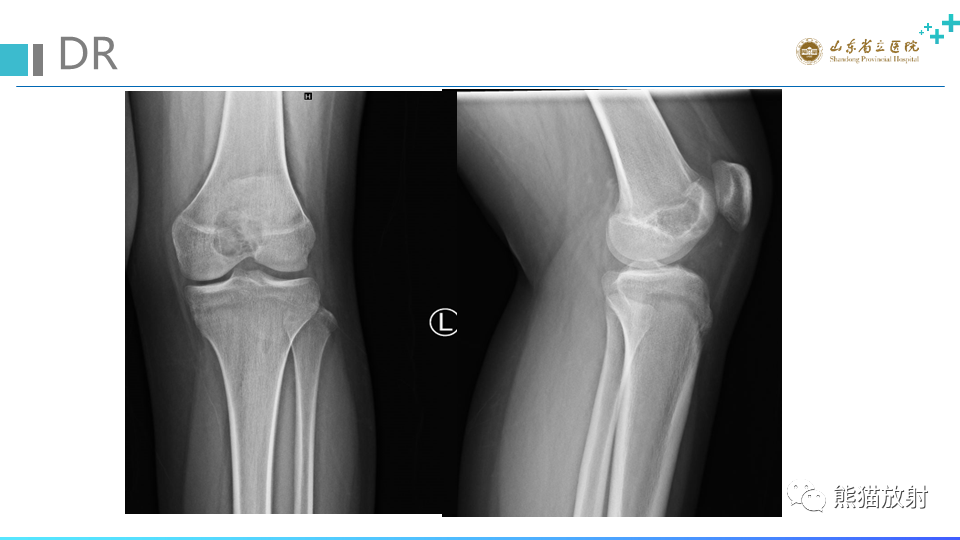

【病例】股骨远端动脉瘤样骨囊肿ABC VS 软骨母细胞瘤-3

【病例】股骨远端动脉瘤样骨囊肿ABC VS 软骨母细胞瘤-4